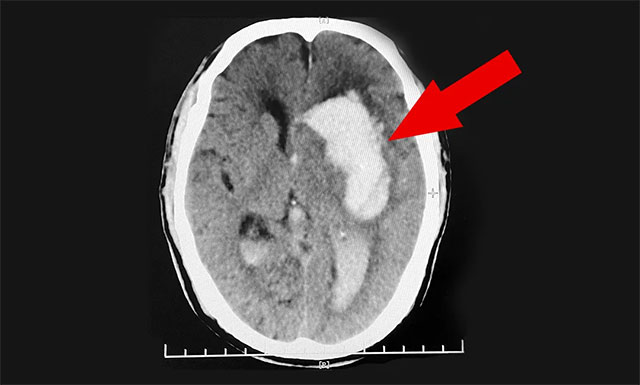

送到醫(yī)院后,緊急行頭部CT檢查,根據影像提示及其他相關檢查,患者程先生左側基底節(jié)區(qū)腦出血,并破入腦室,且出血量很大,臨近功能區(qū);伴左側高顱壓,其雙側大腦半球深部多發(fā)腔梗,情況非常危急。醫(yī)生把情況告知郭女士,若手術治療風險很大,即使保住了生命,也很可能長期偏癱在床,讓她及家屬做好心理準備。郭女士聽后感到“天塌了一般”,簡直無法接受。

“患者緊急轉入我院,當時其格拉斯哥昏迷 (GCS) 評分僅有7分 (GCS總分為15分,分數越低其意識障礙越重),處于昏迷狀態(tài),意識障礙比較嚴重,不能言語,右側肢體活動障礙嚴重;且患者歲數較大,出血范圍較廣,出血量大約為50ml,情況危急不容樂觀……”,潘仁龍主任這樣回顧道,對患者程先生剛入院時的危重病情至今歷歷在目。

▲ 患者突發(fā)腦出血昏迷不醒,病情危急需及時手術

鑒于患者病情危重,潘仁龍主任緊急組織專家團隊會診,根據患者目前的病情、病癥及影像檢查結果,潘主任與吳博士一致認為患者程先生腦出血嚴重,已破入腦室,出血量又大,且左側高顱壓,其血壓收縮壓當時更是高達208mmHg,如果不及時手術治療,還會有再次出血的風險,因此患者需及早手術清除顱內血腫和降顱壓,否則隨時會有生命危險。